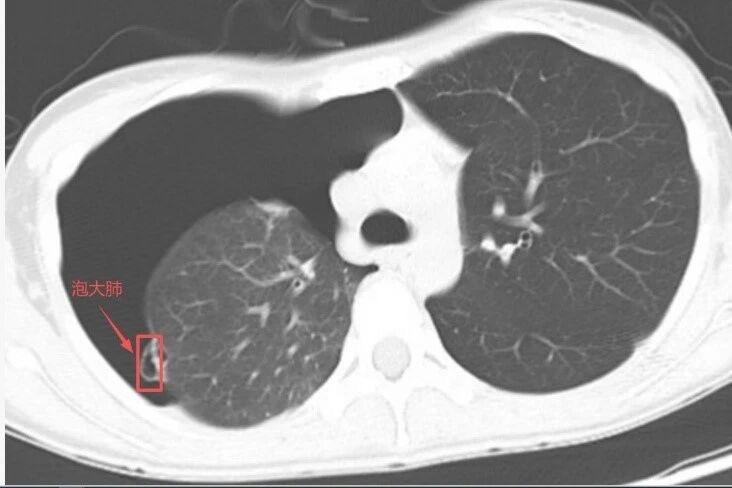

胸部CT:不仅能看到胸腔内无肺纹理区及肺压缩边缘,还能看到明显的肺大泡(箭头所示)。